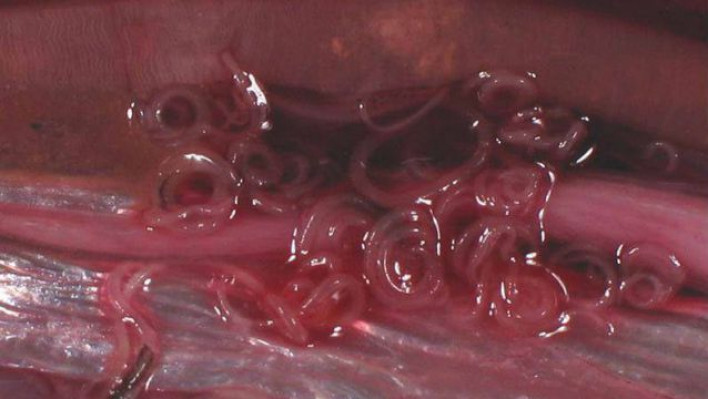

Հյուսիսային Կորեայից փախած զինվորի մարմնից սարսափելի մակաբույծներ են հեռացնում

Հյուսիսային Կորեայից Հարավային Կորեա փախած զինվորը գտնվում է բժիշկների տակ անգիտակից վիճակում և արհեստական շնչառությամբ:  Հարավկորեական բժիշկները նրա բուժմամբ են զբաղված և փորձում են կյանքի վերադարձնել: Վիրաբույժները նրա օրգանիզմից տասնյակ որդեր են հեռացրել, որոնցից մի քանիսի  երկարությունը հասել է մոտ 30 սմ-ի, այս մասին հաղորդում է  Fox News-ը: Ինչպես հաղորդում է աղբյուրը, այս պահին զինվորի վիճակը կայուն է: Զինծառայողը փախել է Հյուսիսային Կորեայից դեպի Հարավային Կորեա է: Փախչող զինվորի վրա կրակել էին մոտ 40 անգամ: